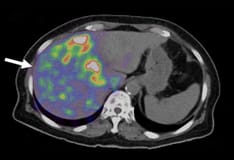

Ultrasonography of the liver.

Hepatic parenchyma and blood vessels as seen on ultrasound.